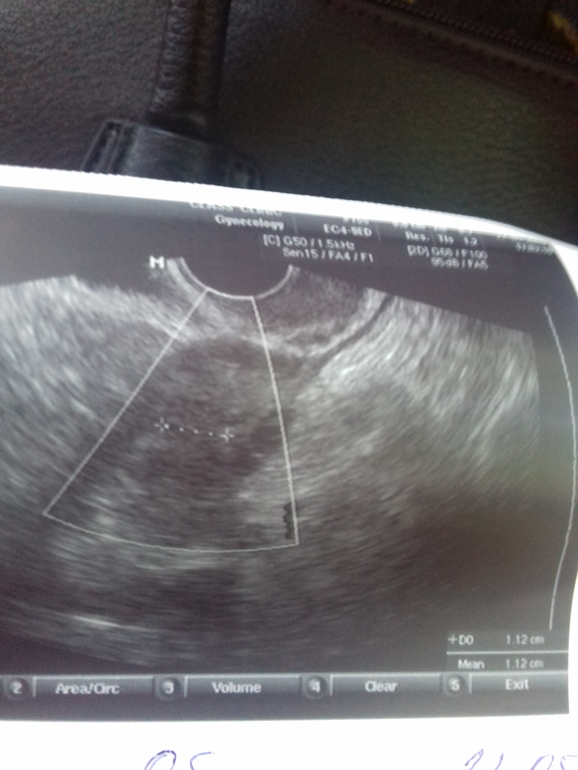

ФолликулометрияСходила на узи. Нашла жт. Но нет выраженного кровотока. Что это значит. Я так понимаю,не хватка прогика,так я дюфастон пью.Что она мне сказала,то что эндик пушистый,готов к оплодотворению. Не взяла денег с меня. Сходила блин.

Меня сейчас волнует жт,которое без выраженного кровотока,т.е. очень слабый. Гиня сказала,что это может быть если яйцеклетка не дозрела или перезрела или фолликул был пустой. Короче обламала мое настроение чудесное.